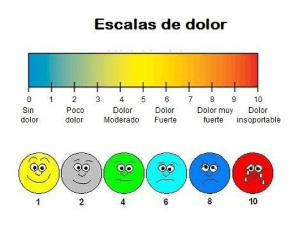

Escala Visual Analógica y sus usos en fisioterapia.

“En esta vida no todo es blanco o negro, sino que siempre hay una escala de grises desde las que mirar las diferentes situaciones a

Las escalas de valoración en fisioterapia II

“Toda la ciencia no es más que el refinamiento del mensaje cotidiano” Albert Einstein. En la anterior entrada del blog, veíamos como las escalas de

Escalas de valoración en fisioterapia.

“ La importancia de tener puntos de referencia y valores sobre los que contrastar la información obtenida, hace más científica la fisioterapia” Profesor Anónimo de